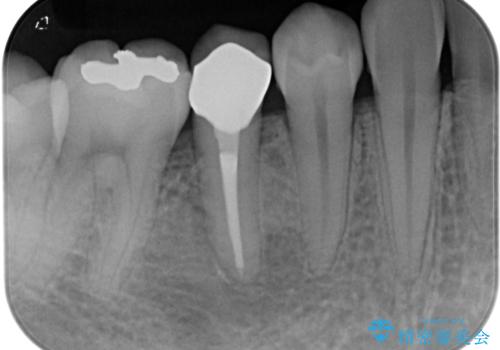

以前通われて医院にて、再度根管治療が必要であると伝えられていたようですが、レントゲン写真などの診察を行った結果、再根管治療が必要な状態でした。

レントゲン写真より、当該歯周囲に大きな透過像があり、歯槽骨が炎症により吸収している様子が認められます。

根管治療を行った歯はクラウンによる補綴治療が望ましく、来院時にはクラウンが装着されていなかったため、根管治療を再度行いやすい環境でした。

根管治療後9ヶ月で撮影したレントゲン写真より、歯根周辺の透過像が十分に消失している様子が認められました。